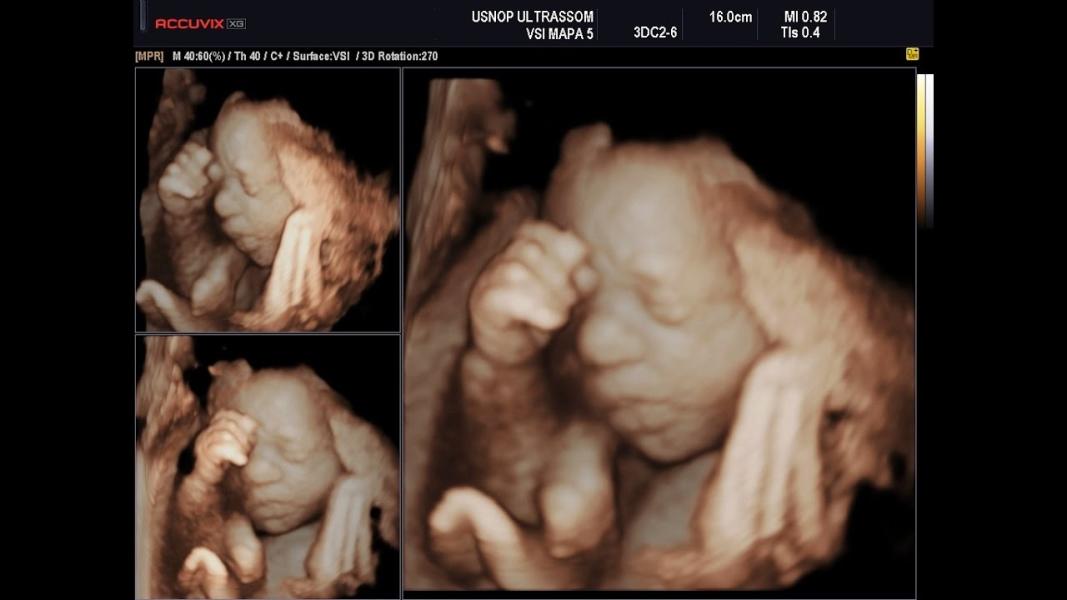

dia do ultrassom

doutor Luiz

aqui o utrasoso

sim eu achei que ele estava de 3 messe

ele está de canta semanas

ele está de 4 messe

E da pra sabe o sexo do bebe